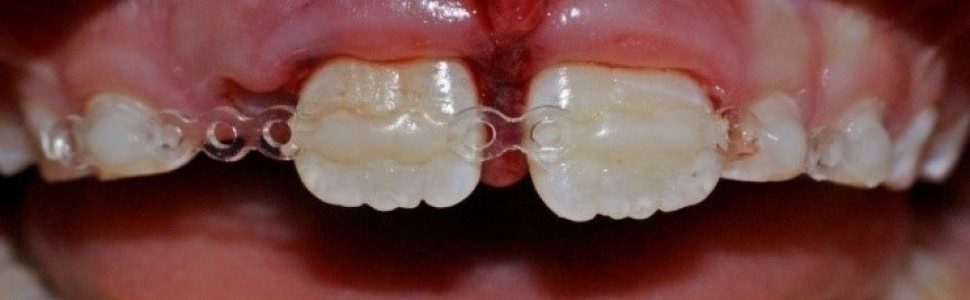

Szyny stosowane są w leczeniu urazów, którym towarzyszy uszkodzenie więzadeł ozębnej. Różnorodność szyn urazowych pozwala dentyście dobrać odpowiedni materiał, który spełnia wymagania danej sytuacji klinicznej i pacjenta. Celem pracy jest ocena wiedzy lekarzy dentystów na temat szynowania zębów po urazach. Badanie miało charakter ankietowy. Wzięło w nim udział 264 lekarzy dentystów. Wynik uzyskane z formularza online poddano analizie statystycznej. Z badań wynika, że wiedza lekarzy dentystów na temat stabilizacji zębów po urazach jest niewystarczająca. Wśród lekarzy dentystów stomatolodzy dziecięcy to specjaliści, których wiedza na temat stabilizacji pourazowo uszkodzonych zębów jest znacząco wyższa i ta grupa lekarzy wydaje się odpowiednio przygotowana do leczenia pacjentów z urazami zębów.

Dental trauma splints are used to treat teeth injuries involving periodontal damage. The wide variety of trauma splits allows the dentist to choose the material that meets the requirements of a clinical situations and an individual patient. The aim of the study was the assessment of polish dentists’ knowledge about splinting teeth after trauma. A questionnaire survey was conducted. 264 dentists took part in the study. The result obtained from the online form was statistically analyzed. Research shows that the dentists’ knowledge about the stabilisation of teeth after injuries is insufficient. Among dentists, pediatric dentists are specialists whose knowledge of the stabilisation of injured teeth is signifi cantly higher, and this group of professionalists seems to be adequately prepared to treat patients with dental trauma.